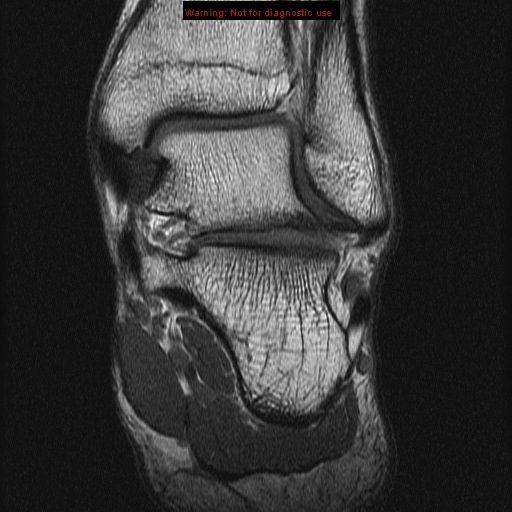

lateral malleolus

anterior tibiofibular ligament

posterior tibiofibular ligament

anterior talofibular ligament

posterior talofibular ligament tendon of tibialis posterior

medial malleolus

fibula

sustentaculum tali

anterior process of the calcaneus

fibula cuboid